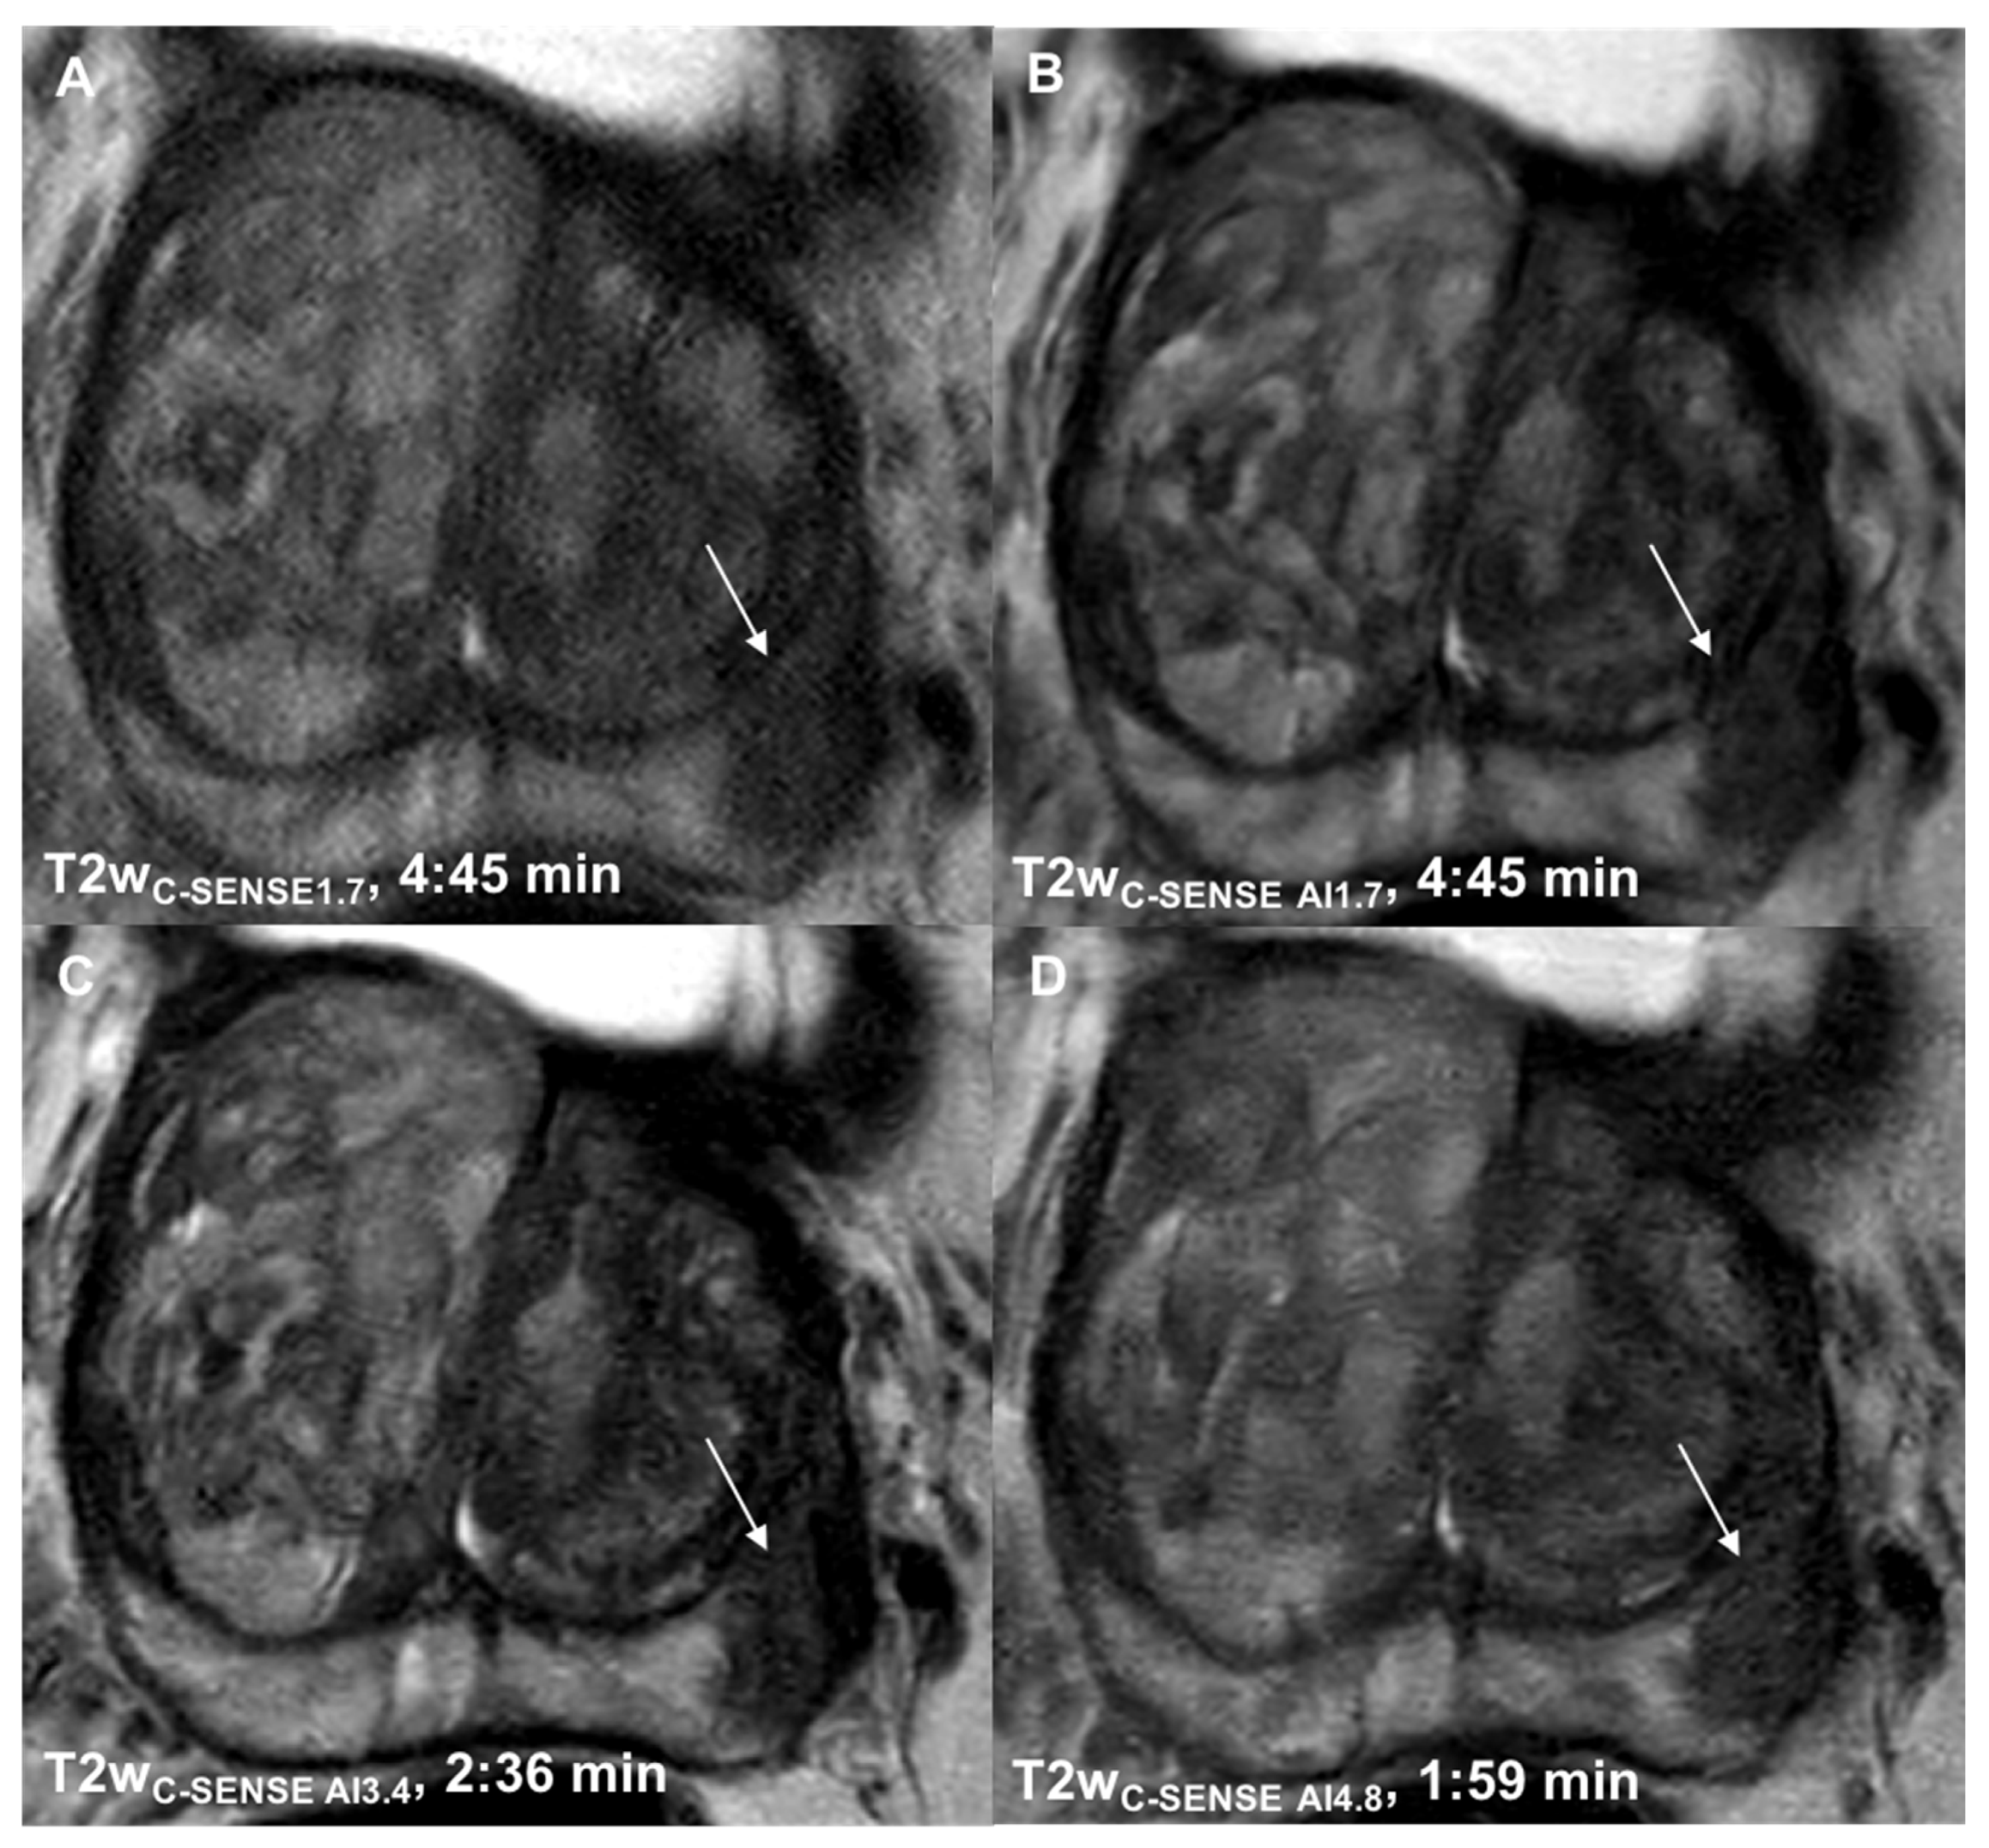

3.1. Determination of Suitable Acceleration Factors

| Scan time (min) | 4:45/2:36/1:59 | 5:12 (b50-1000) 3:48 (b1500) |